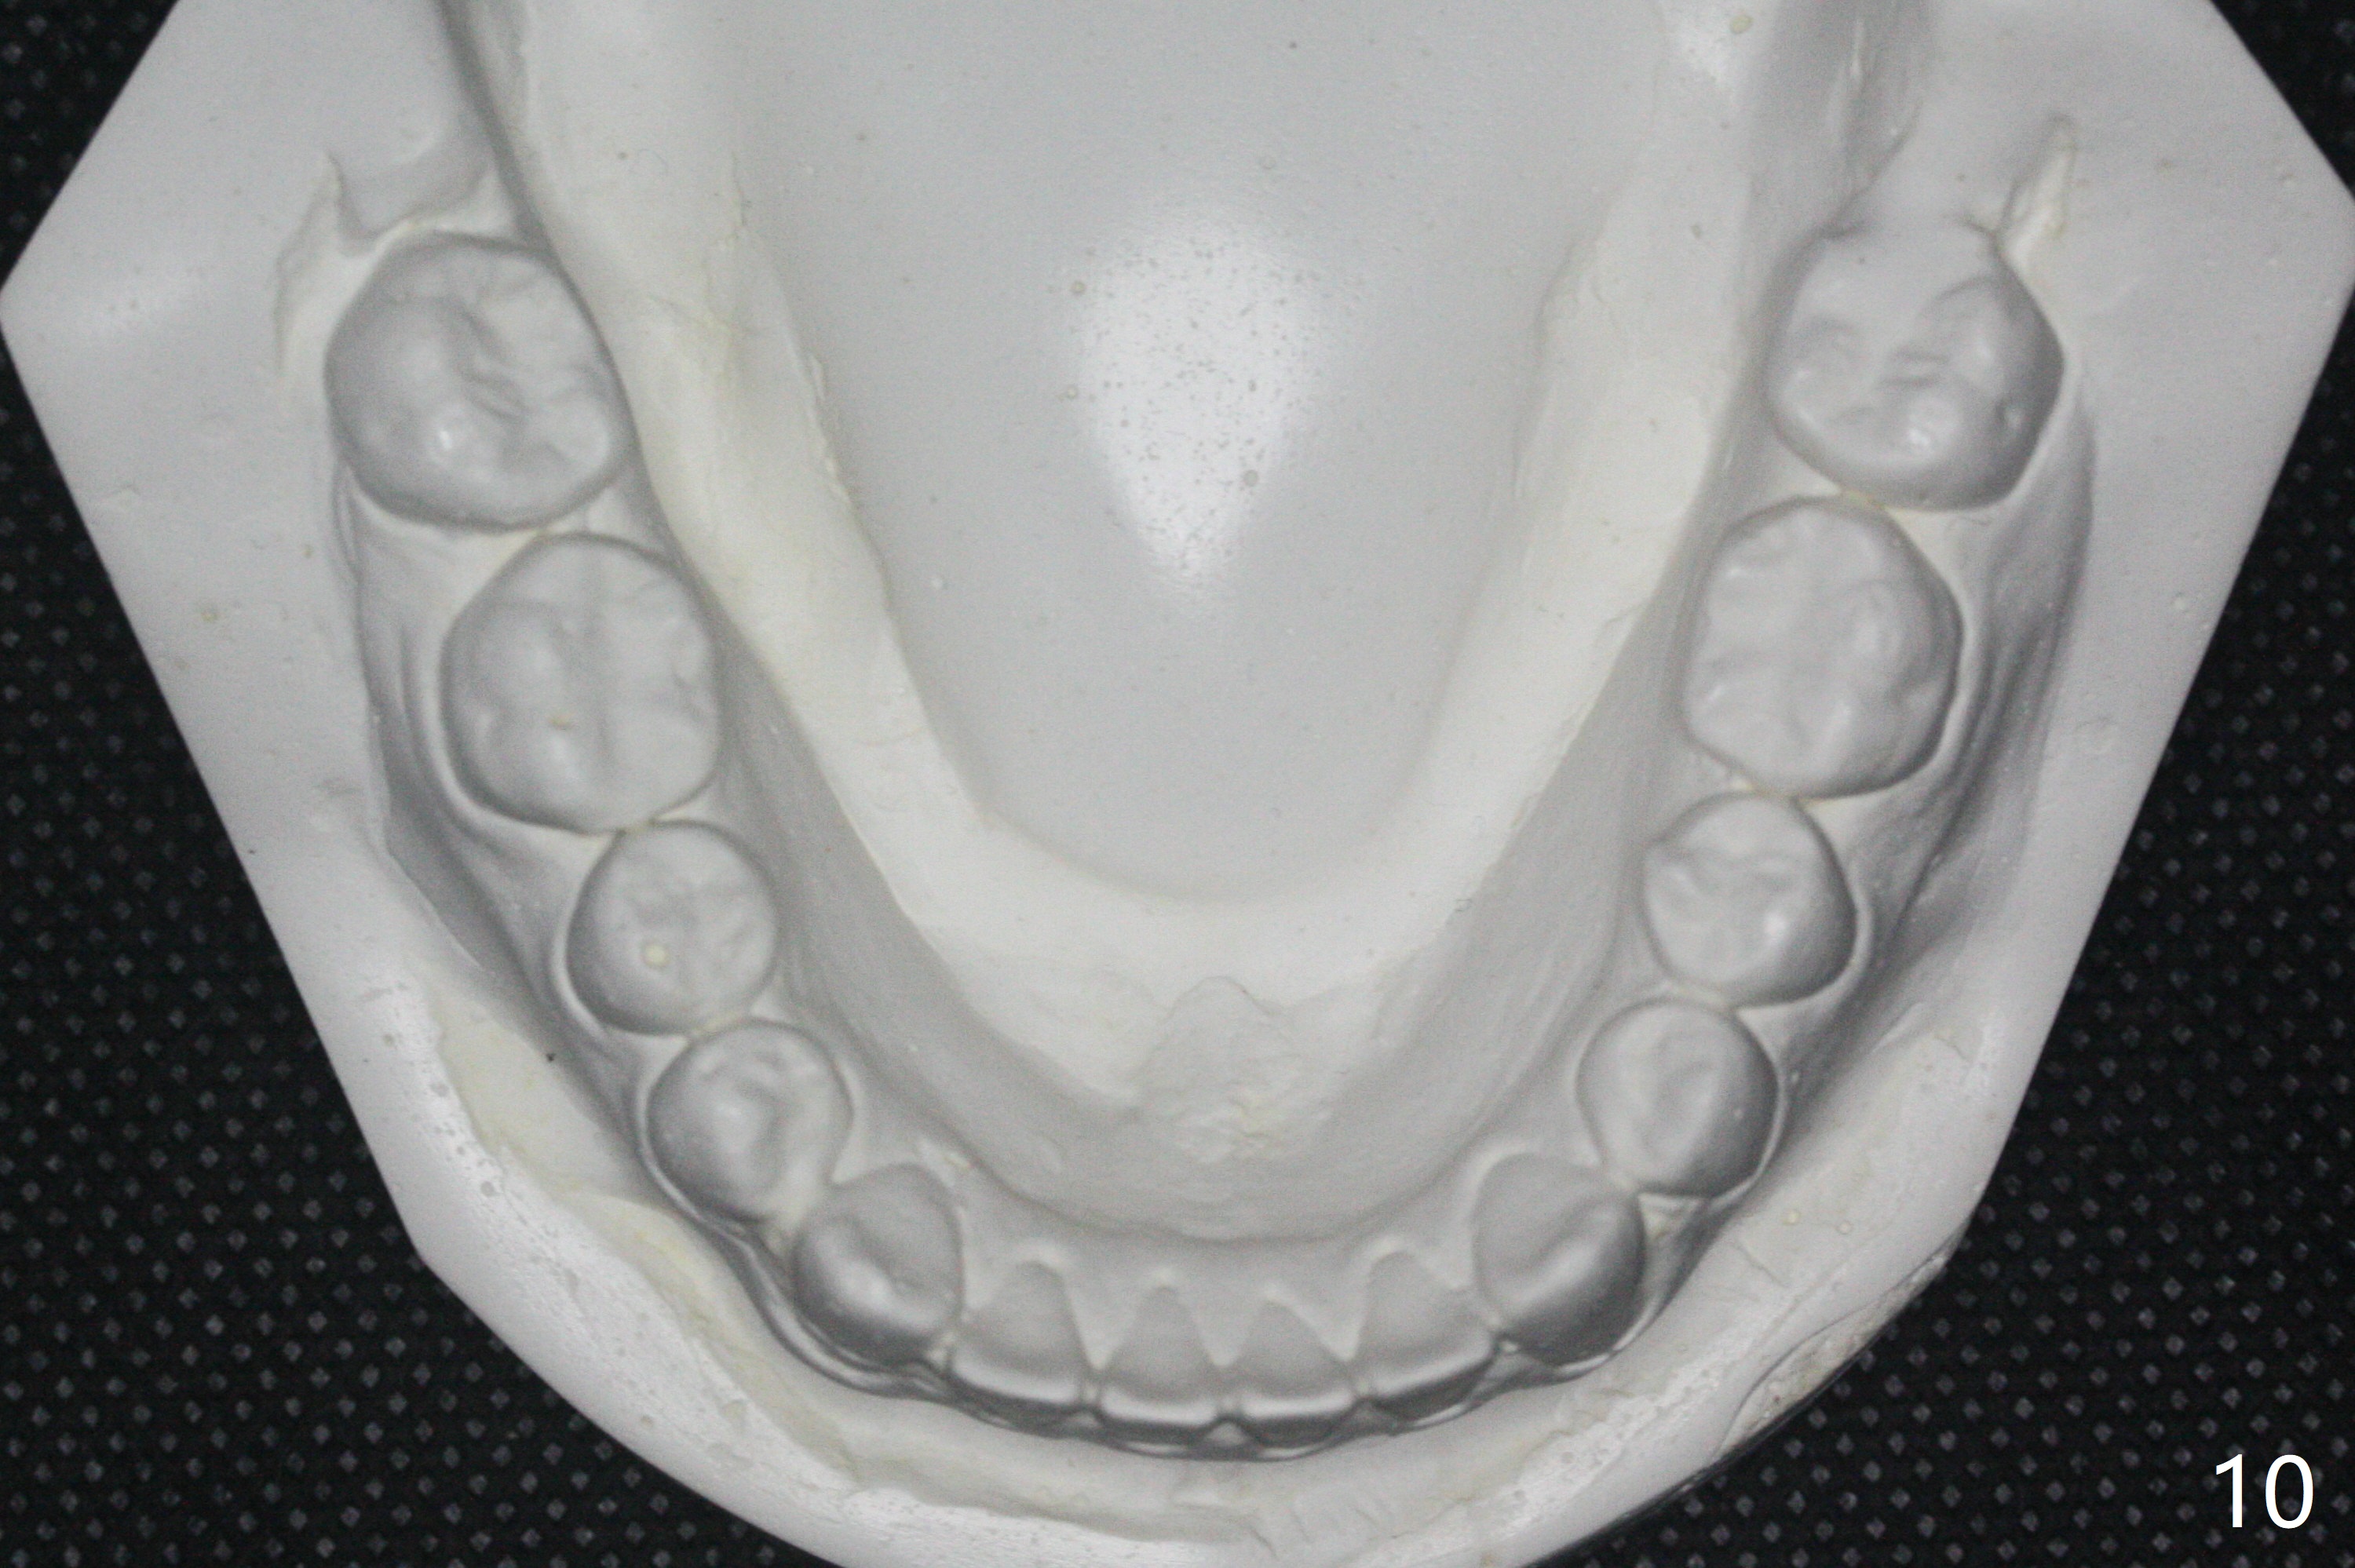

15岁男完成矫正1年9月,右侧后牙咬合理想(图二),上中切牙长轴改善,侧切牙torque不够完善(图四),左侧后牙咬合二类𬌗(图六,需要牵引),磨牙缝隙大(图八,十),造成食物堵塞,以后尽量避免使用磨牙bands,尤其是成人。